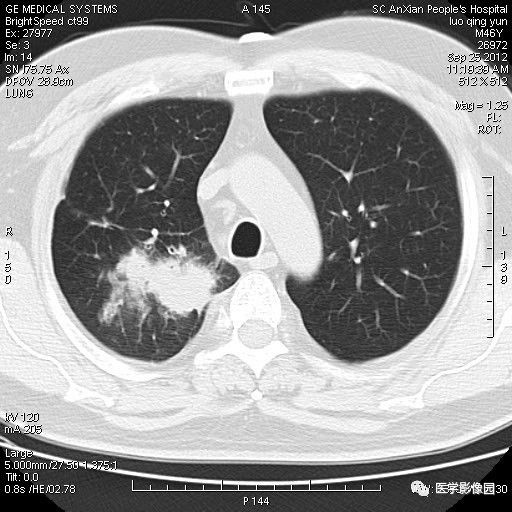

【病例】右上肺炎性假瘤1例CT影像表现

患者男性,46岁,临床未提供病史。

影像学表现:右上肺见不规则团块状高密度阴影,略有分叶级毛刺,边缘模糊,邻近胸膜增厚,增强扫描呈轻中度强化。

诊断结果:右上肺炎性假瘤

本病影像学表现无绝对特征性。单发多见,多位于肺表浅部位,多呈圆形或椭圆形,直径多在2-5cm或更大;多有假包膜,边缘多清晰光整,有时也毛糙,并可有分叶或毛刺;邻近胸膜局限性增厚、牵拉,病灶边缘呈桃尖样突起即桃尖征(尖端指向胸膜);增强扫描多呈中度均匀强化,持续时间较长。亦可显著强化。